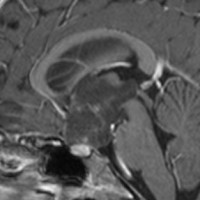

画像の特徴

幼児の視路の毛様粘液性星細胞腫です。T2強調画像(左側)で白く高信号に写るのが特徴です。ガドリニウム増強ではまだらになっていますが,均一に真っ白に高信号になることも多いです。乳幼児のものは,ドロドロに柔らかい腫瘍です。